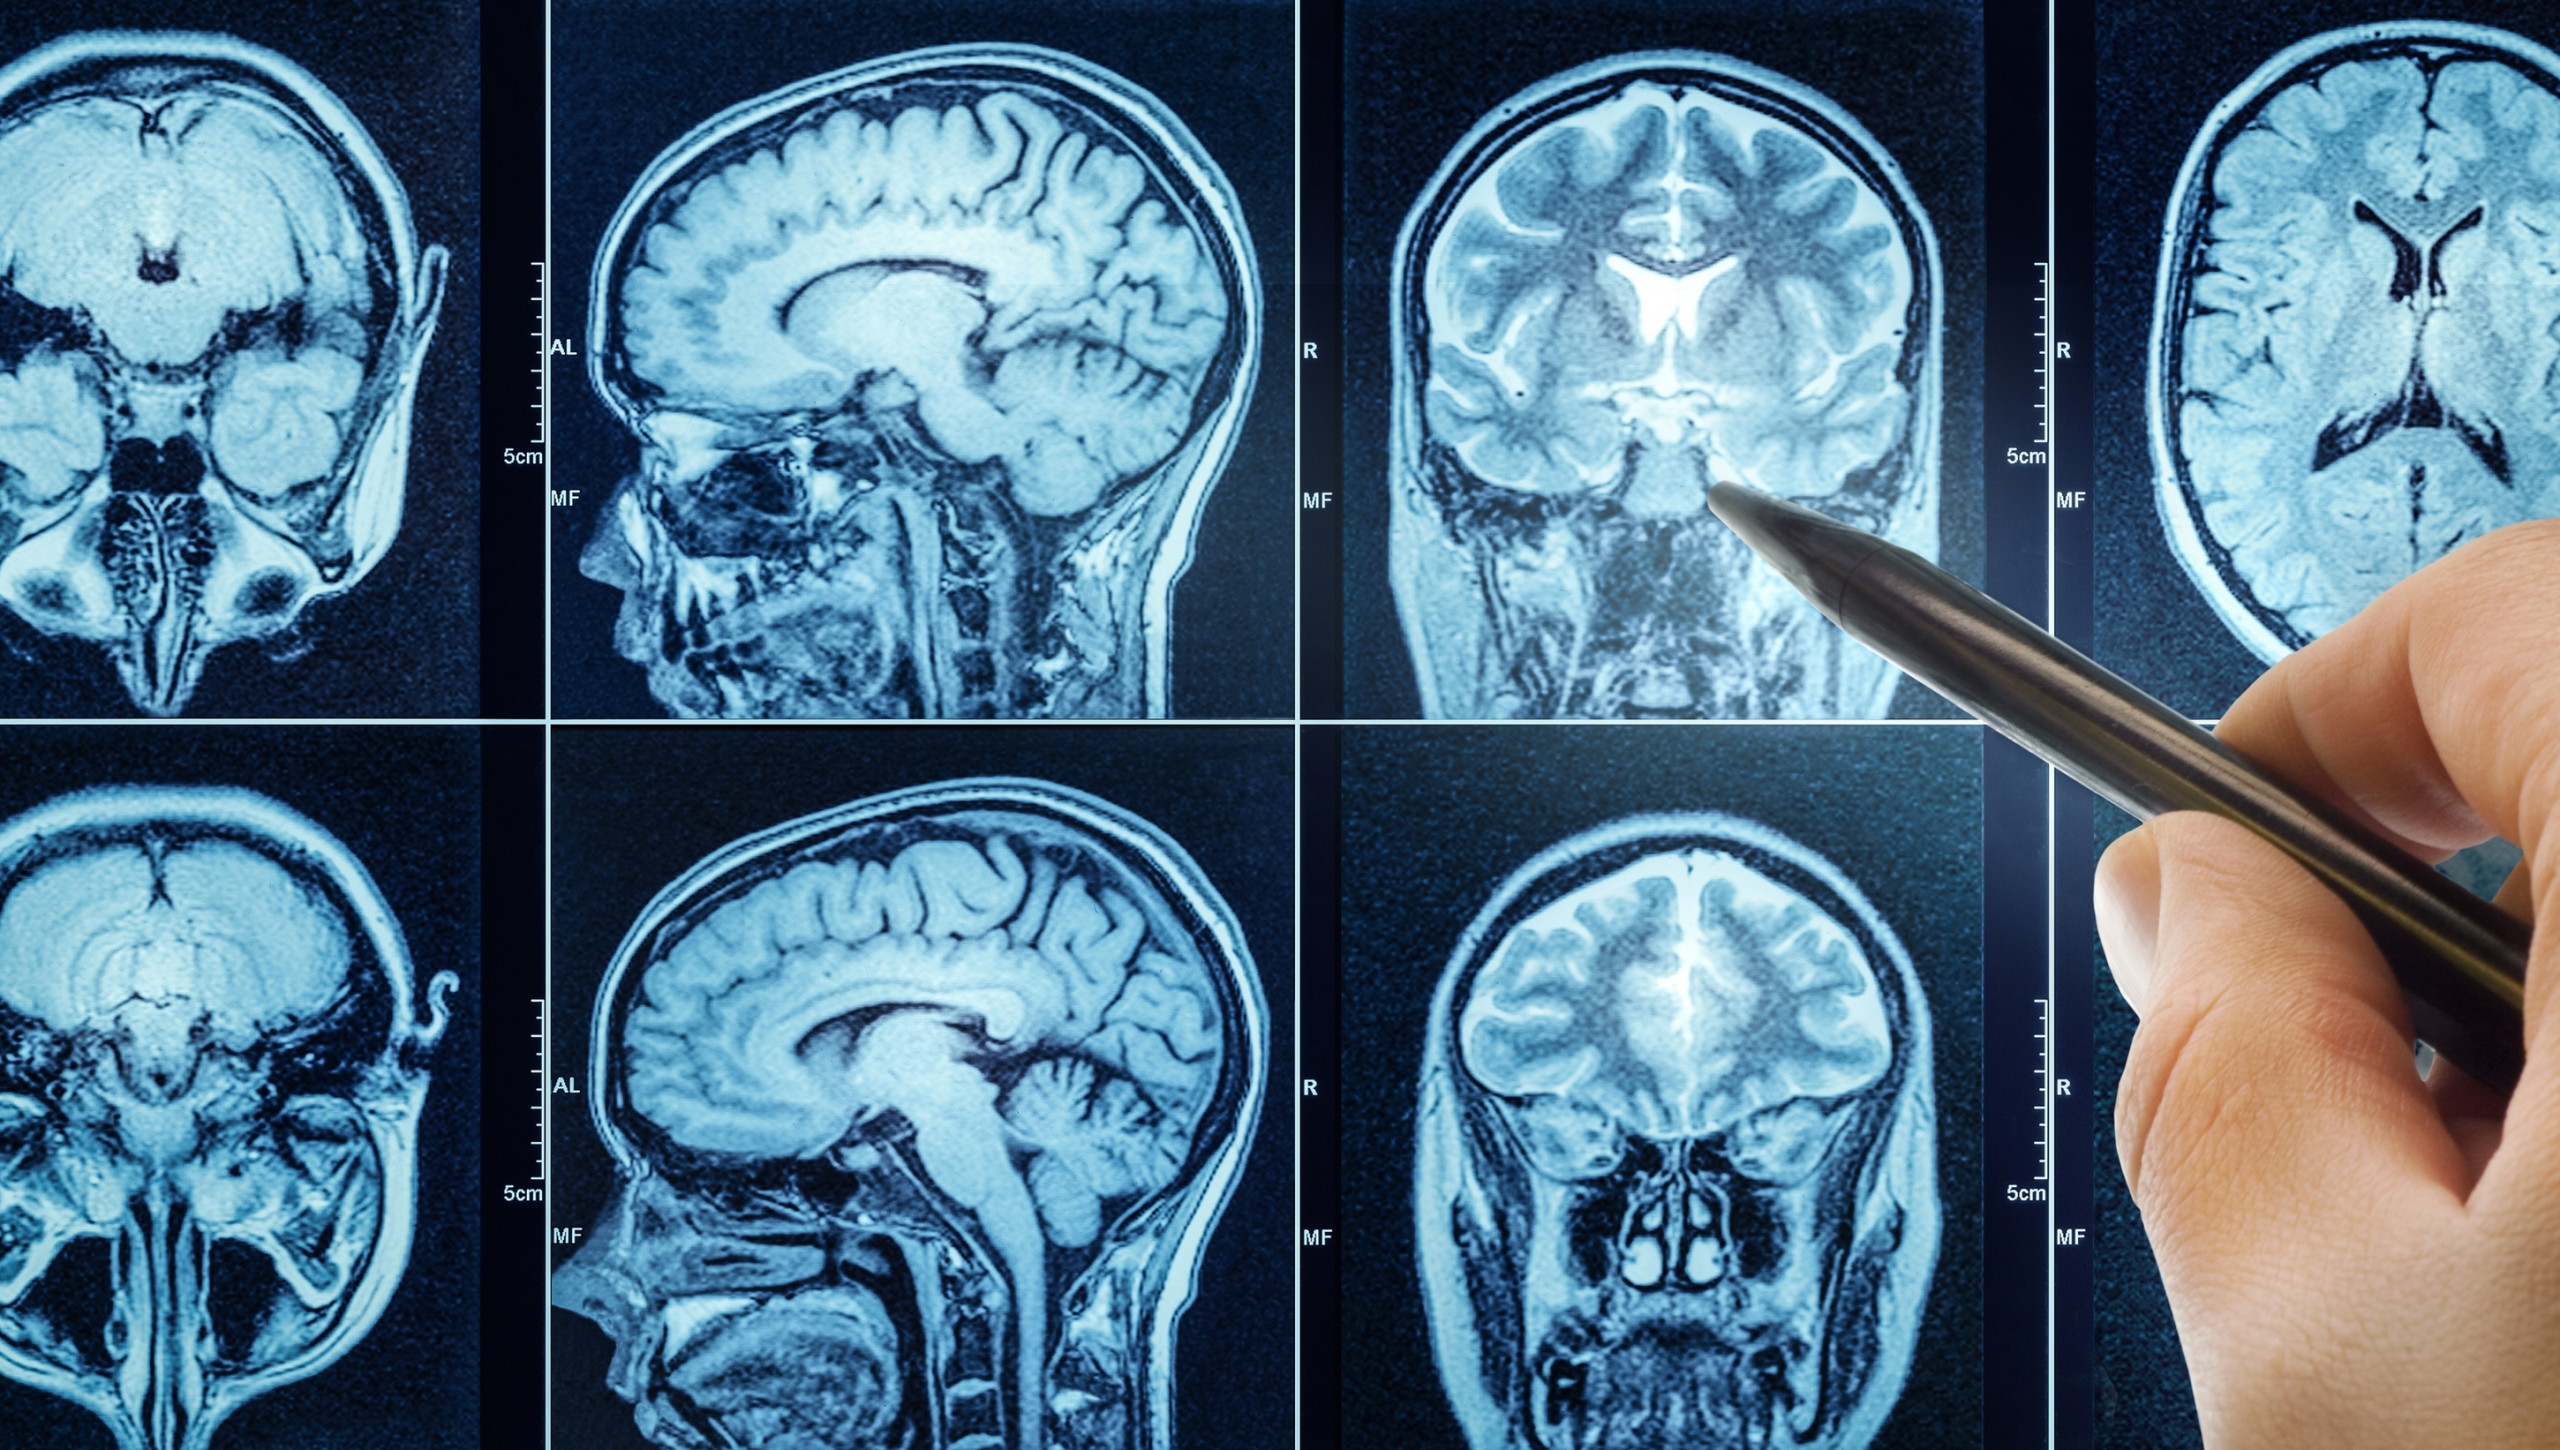

Pesquisadores da Universidade da Pensilvânia descobriram que a hidralazina, um remédio usado há quase 70 anos para tratar pressão alta, pode ter um novo efeito: interromper o crescimento de tumores cerebrais agressivos. A equipe divulgou os resultados na Science Advances, revelando pela primeira vez o mecanismo de ação do medicamento e sugerindo novas possibilidades de tratamento.

O estudo também revelou uma conexão biológica inesperada entre distúrbios hipertensivos e câncer cerebral. Pesquisas anteriores já sugeriam que tumores como o glioblastoma dependem da ADO para sobreviver em ambientes com pouca oxigenação. Contudo, faltava um inibidor eficaz para explorar essa relação.

Com a colaboração de bioquímicos e neurocientistas, os pesquisadores testaram a hidralazina em células de glioblastoma e os resultados mostraram que:

- O mesmo mecanismo que regula a contração dos vasos também ajuda as células tumorais a sobreviver.

- Bloqueando a ADO, o remédio induz um estado de “senescência”, fazendo com que as células parem de se multiplicar sem causar inflamação.

- Diferente da quimioterapia tradicional, a hidralazina consegue interromper o crescimento tumoral.

Esses resultados sugerem que um remédio para pressão alta pode ser usado como um novo tratamento contra tumores cerebrais agressivos.